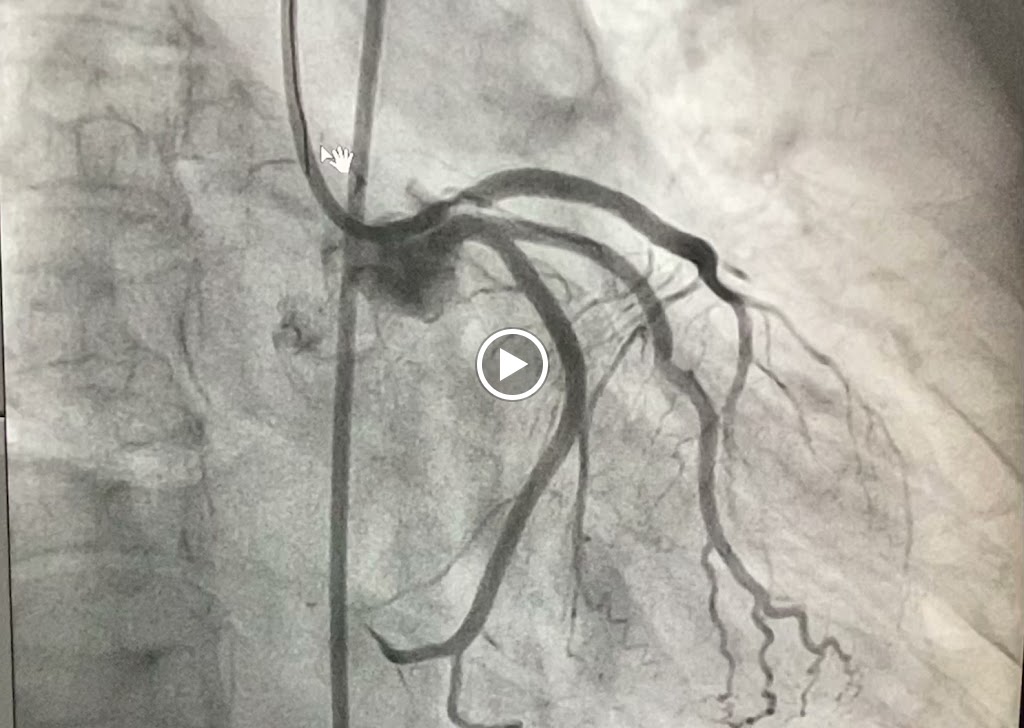

Heart Screening, High Blood Pressure, Stroke Screening, Peripheral Arterial Disease, Aneurysm Screening, Sudden Death Screening, Nuclear Stress Test, Best Cardiologist In Pune. I am passionate about treatment of heart attack using most modern technologies of primary angioplasty and delivering quality cardiac healthcare in India. If you want me to manage your dear one's case in Pune, please call me directly on my phone 7719972828 and I will manage the rest. thanks

I had my coronary angiography done by Dr Rahul sir.He has excellent skills,confidence and knowledge of his subject and he is very competent cardiologist. He trained at Cambridge and New York and this is evident in his skillset. Highly recommended

We underwent an angioplasty procedure, for my father and I cannot thank Dr. Rahul Sawant Sir enough for the exceptional care and professionalism throughout the entire process. From the initial consultation to the post-procedure follow-ups, Dr. Sawant Sir was incredibly thorough, compassionate, and reassuring. The procedure itself went smoothly, and we felt it was in the safest hands. Dr. Rahul Sawant Sir took the time to explain everything in detail, addressed all our concerns patiently, and ensured we are comfortable and well-informed at every step. Thanks to Dr. Sawant Sir and the wonderful team, I highly recommend Dr. Rahul Sawant to anyone in need of cardiac care -- truly one of the best in the field!